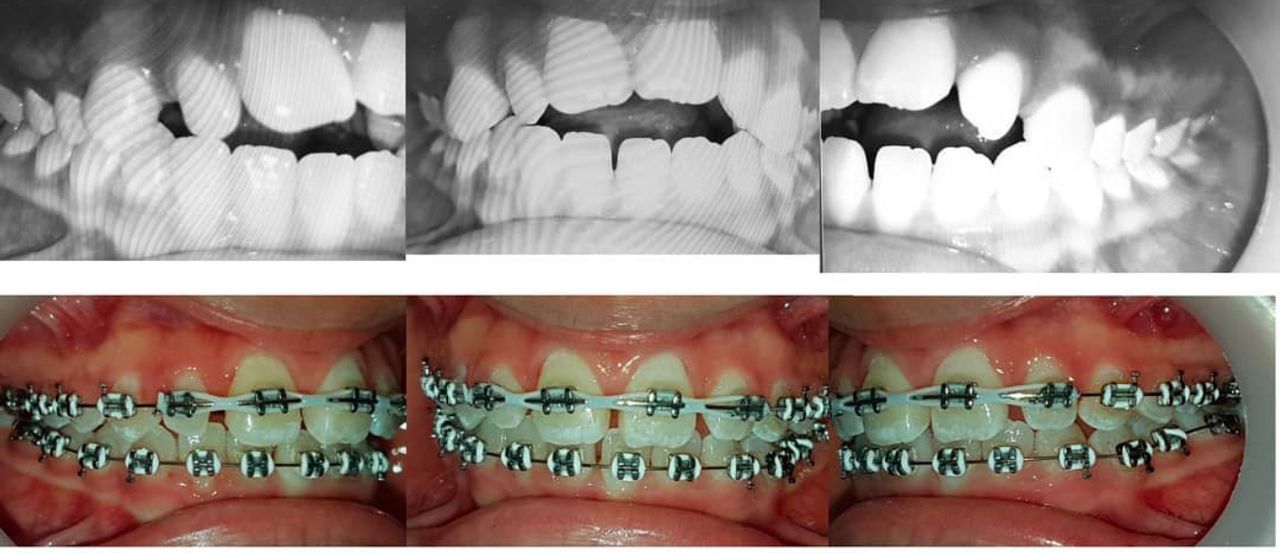

Ortodoncista y Ortopedista maxilar funcional con dedicación exclusiva y trayectoria académica. Mi enfoque es simple: técnicas modernas, aparatología cómoda para resultados excelentes con un trato amable y honesto. me apasiona usar mi experiencia para que vuelvas a sonreír con seguridad. Espero verte pronto en mi consulta!

• Ortodoncia

• Ortopedia Maxilar